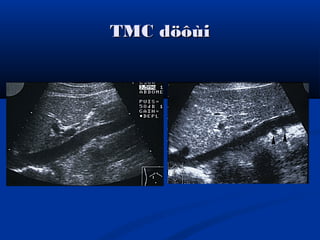

TMC döôùiTMC döôùi

ÑMC buïng vaø TMC döôùiÑMC buïng vaø TMC döôùi